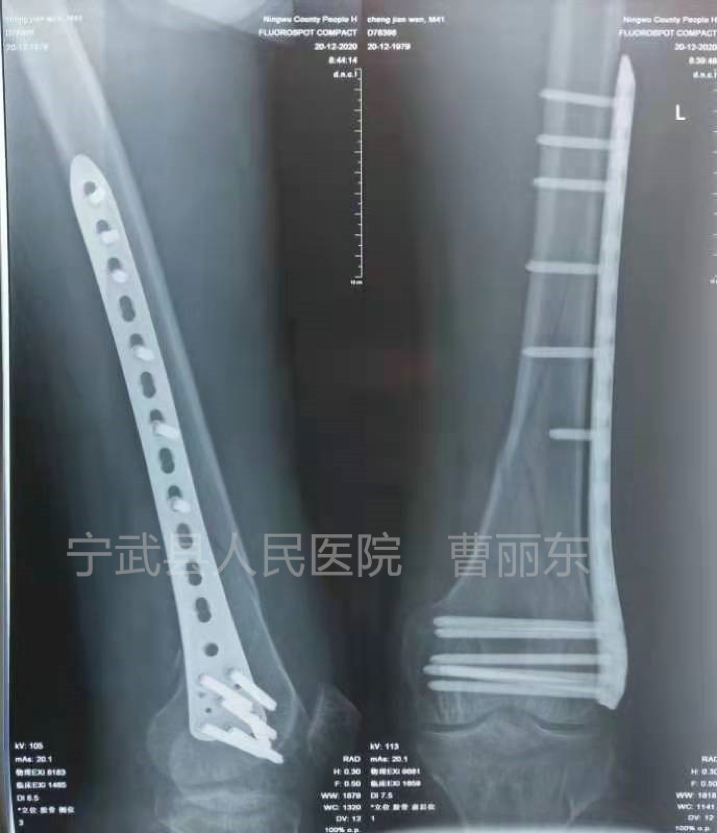

一例股骨髁骨折

微创钢丝捆扎复位

复位后安放钢板,拧入螺钉固定

术后拍片骨折复位良好,内固定钢板位置良好。

这是一例胫骨中下段螺旋形骨折,同样通过微创置入钢丝捆扎复位,置入钢板